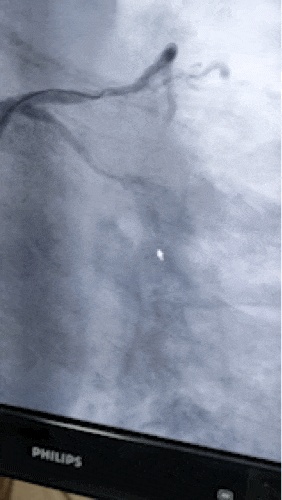

术中王新云团队在血管内超声引导下,在选择微导管及强支撑力导管支持下,使用多种不同硬度及特性的钢丝反复调整方向尝试,最终通过闭塞段至右冠状动脉远端,同样使用了边支球囊锚定技术使预扩张球囊通过硬度很高的钙化病变处,并扩张再通闭塞多年的冠脉... ...成功在右冠植入支架3枚, 8月份,患者再次入院,同样成功完成了左冠回旋支支架内闭塞再通手术。

开通了回旋支支架内闭塞病变